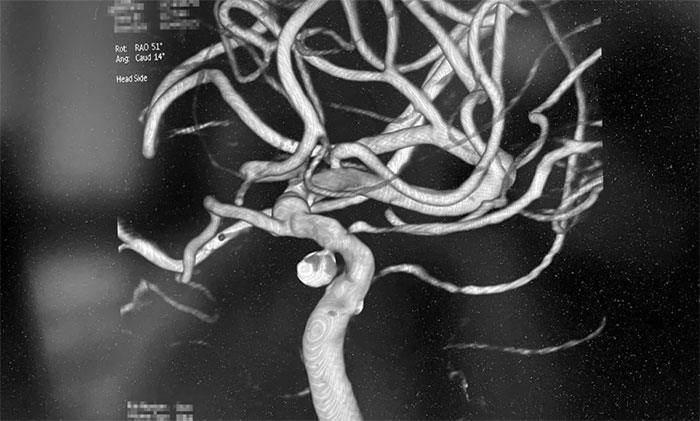

▲ 术后,成功栓塞动脉瘤并开通血管

术中,席刚明教授在王贵平博士及医护团队密切配合下,先对左颈内动脉C6段动脉瘤进行弹簧圈栓塞治疗,经Echelon-10微导管送入弹簧圈,成篮满意后暂不解脱;随后,微导丝引导球囊扩张导管头端置于左侧大脑中动脉M1段,球囊部分覆盖左颈内动脉C6狭窄段,进行球囊扩张,扩张后见左颈内动脉C6段狭窄明显改善,随后释放支架于左颈内动脉C7段至C4段,造影见左颈内动脉、左大脑中动脉、左大脑前动脉显影可。最后,继续栓塞动脉瘤,经Echelon-10微导管送入多枚弹簧圈,填塞满意后解脱,造影见动脉瘤基本不显影;复查造影,行3D造影见左颈内动脉、左大脑中动脉、左大脑前动脉显影可;行支架CT见支架成形满意,行XperCT未见颅内出血,手术圆满完成。